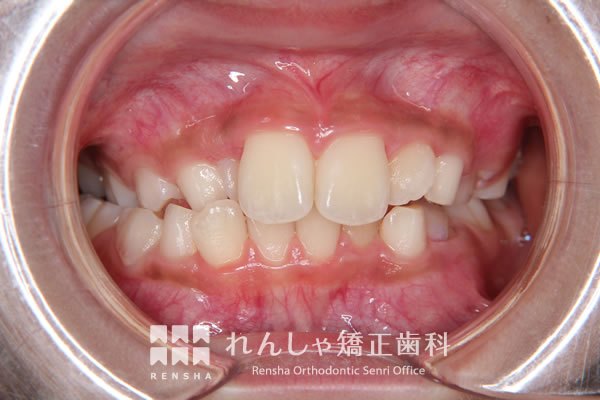

中高生

永久歯列はほぼ完成してしますが、歯列を側方だけでなく後方へも拡大し、埋まっていた右上奥歯を引っ張り出しています。

| 主訴 | 埋まったままでてこない歯がある |

|---|---|

| 診断名 | Angle Class II 小臼歯の埋伏と叢生を伴う上顎前突 |

| 初診時年齢 | 13歳5か月 |

| 装置名 | マルチブラケット装置 |

| 抜歯非抜歯 | 非抜歯 |

| 治療期間 | 2年3か月 |

| 費用の目安 | 約82万円+消費税(検査料金、都度の処置費用等も合わせた総額) |

| リスク副作用 | 歯の移動に伴う軽微な歯根吸収、歯槽骨吸収、歯肉退縮(本症例では軽度の歯根吸収を認めた)、矯正器具装着中のカリエスリスク増大(本症例ではカリエス発生無し) |